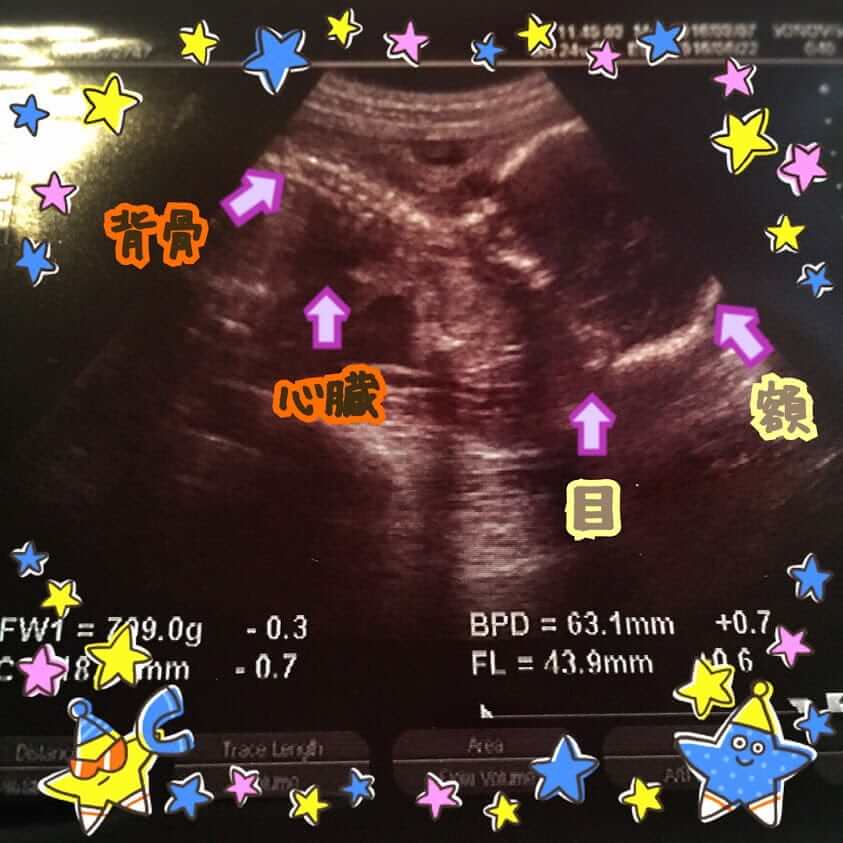

次に腹部超音波検査で、ベビーの体重測定。

・兄は逆子になってしまって、645g。

・弟は変わらず第二横位で、709g。

弟の方が

臍帯付着異常がありますが、今回も成長の差は無く安心しました ε-(´∀`; )

そしてエコー写真はなんだかよく分からないですね!(;´∀`)

その場でモニターで説明されながら見るとわかるんですが、画像にすると荒い。。。

個人的にはおしりを下からとったアングル(太ももの骨と男の子の証が映ってる)がお気に入りです(笑)